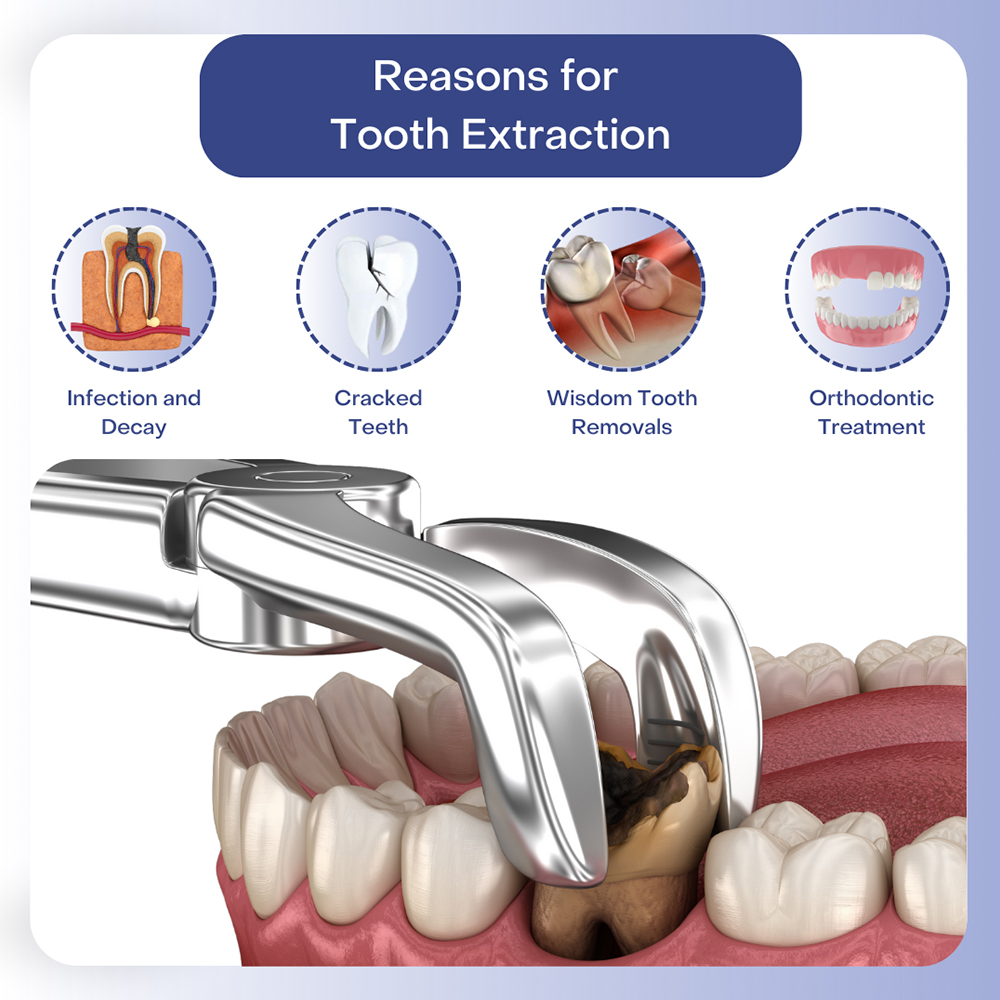

Tooth extraction is a dental procedure in which a tooth is removed from its socket in the bone. While preserving your natural teeth is always the goal, tooth extraction may be necessary when a tooth is severely damaged, infected, or causing other issues. It is often a last resort when other dental treatments (like root canals or fillings) cannot save the tooth.